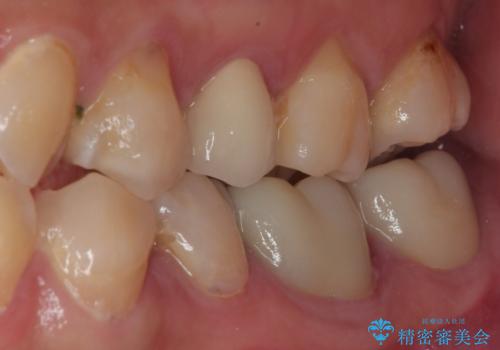

- 左上の前から5番目の金属の詰め物(メタルインレー)が取れたとのことで来院された患者様です。一時帰国中とのことで短期間での治療を希望されていました。土台はファイバーコアがしっかり入っていたため、そのまま利用することにしました。根管治療は症状もなく、レントゲン上でも病変を認めないため患者様と相談して根管治療を行わないことにしました。拡大鏡の視野下において、虫歯を除去して元々の詰め物の範囲も大きいためオールセラミッククラウンに適した形に整えました。

適合もよく、機能的に問題もなく、見た目も満足されていました。